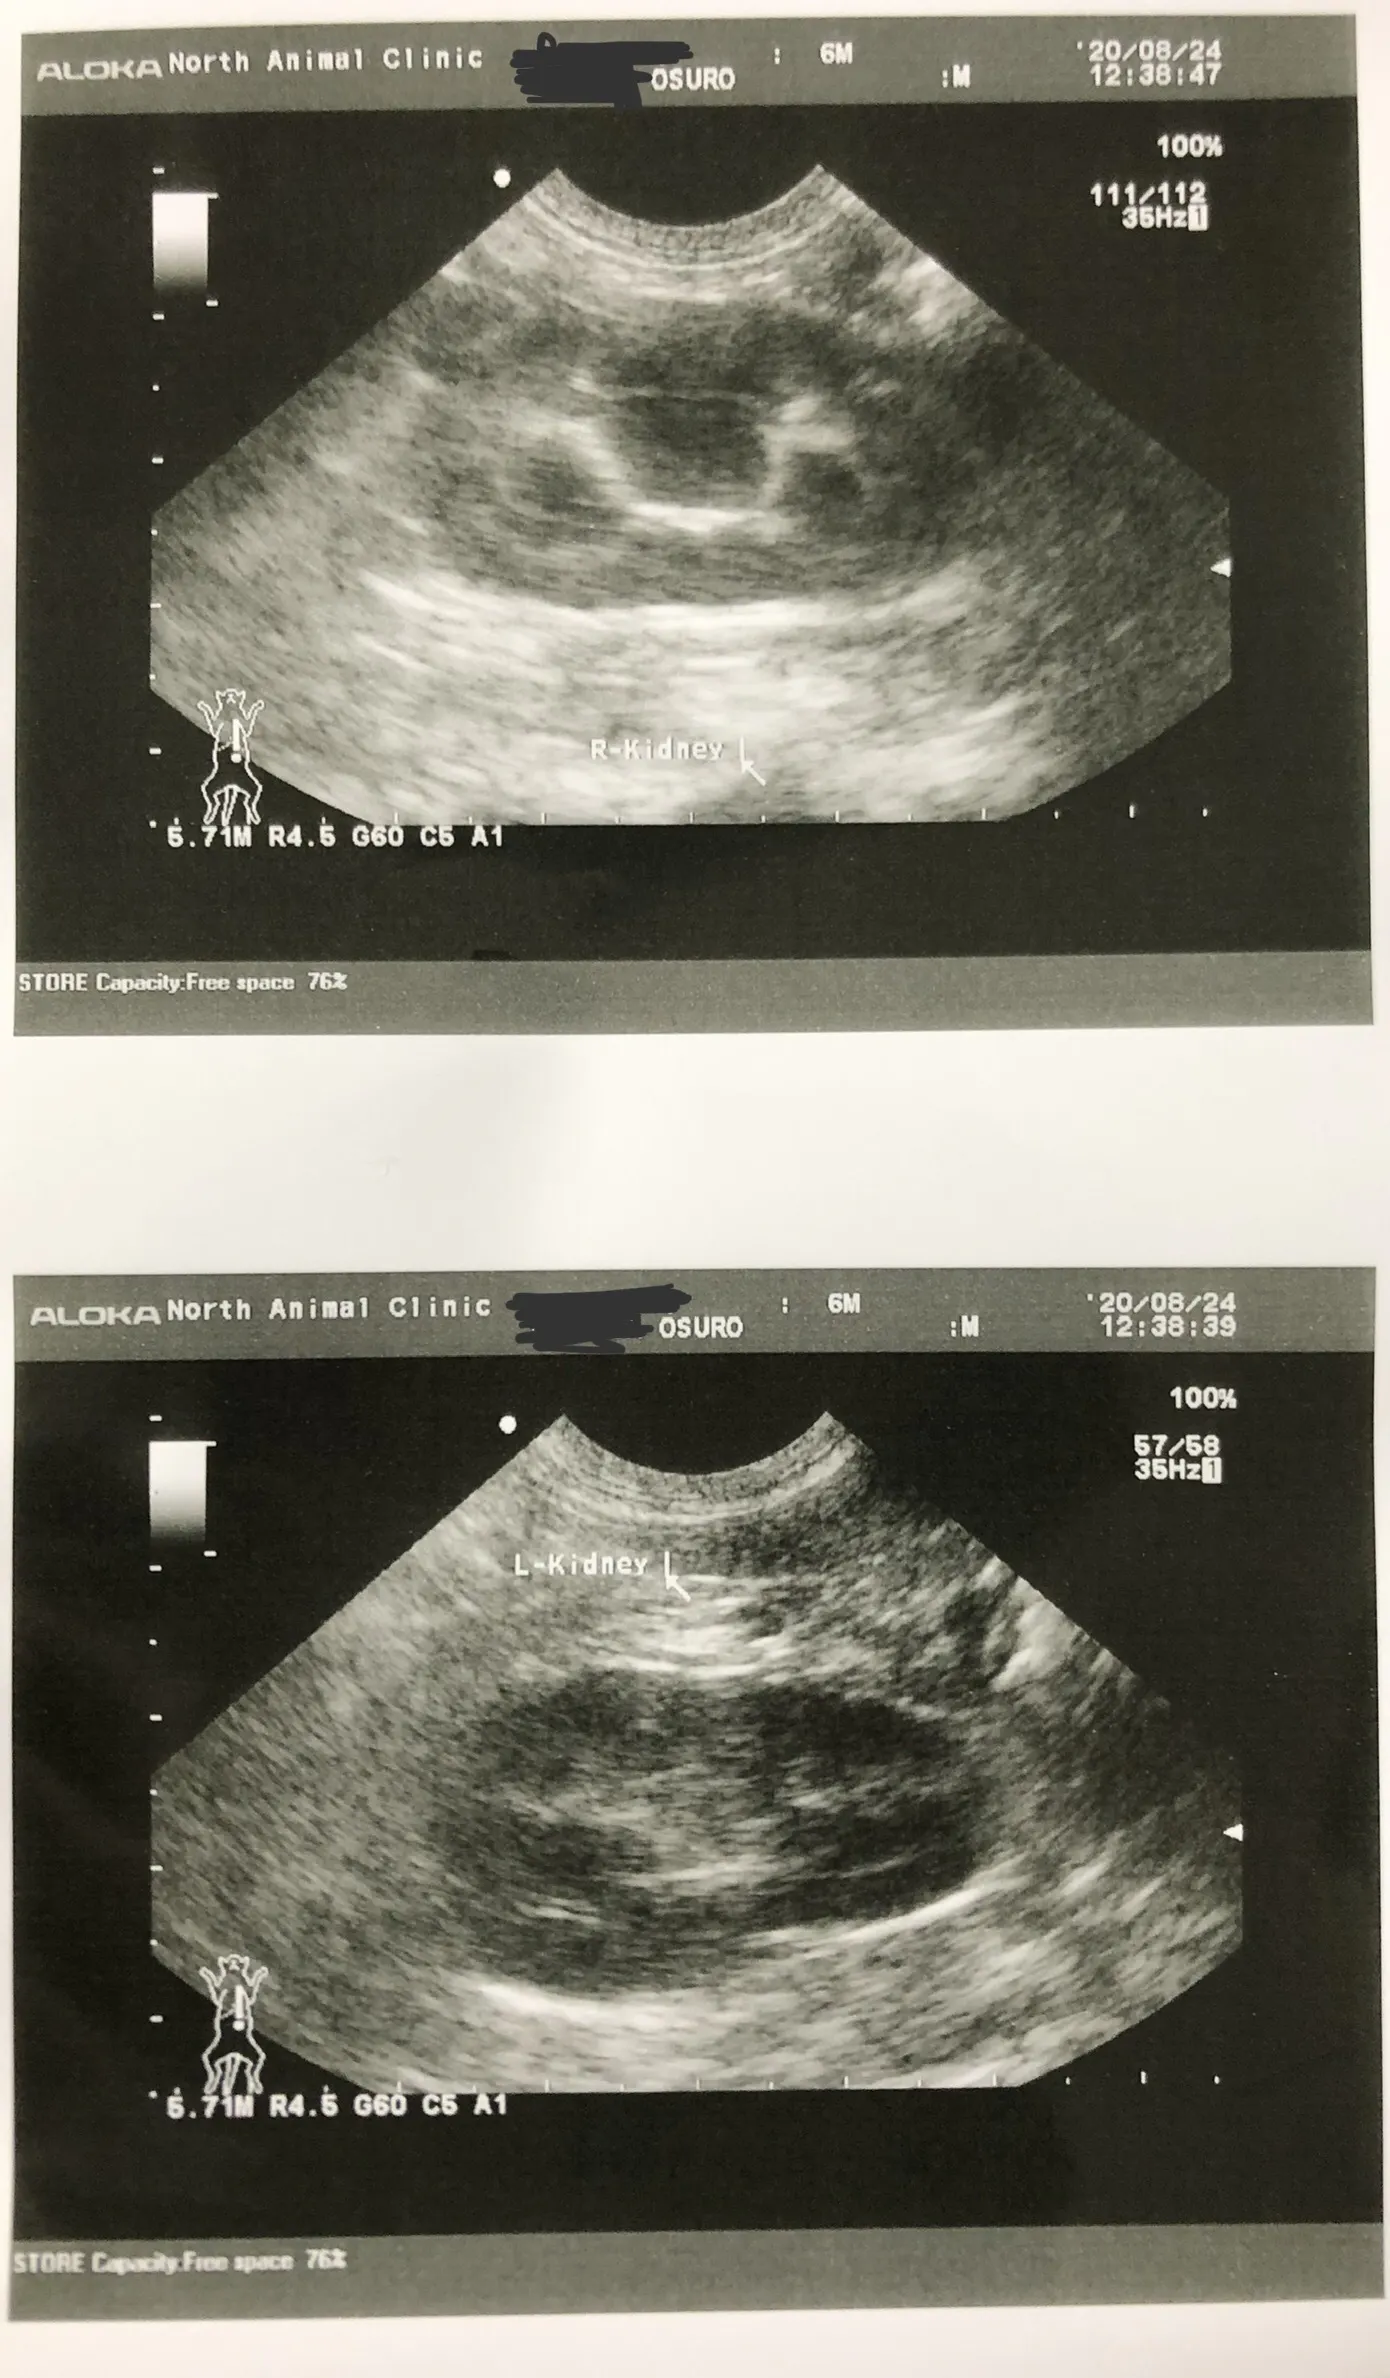

結果は変わっておらず、いろんな病気の検査をすることに。まずは猫エイズ/白血病の検査。こちらは陰性で、続いてエコー検査をしました。するとしこりがあると言われ、どんどん不安が大きくなっていきました。

先生がウイルスの検査をさせてほしいということで、FIPの検査をすることに。このしこりに針を刺して外部検査してもらい、検査結果を1週間待ちました。

診断結果はFIP ドライタイプ 中期でした。ドライタイプは確定診断が難しい場合があり、FIP検査結果が陰性でもFIP症状があり、FIPの治療薬を飲むと効きやはりFIPだったと断定できる場合もあるそうです。